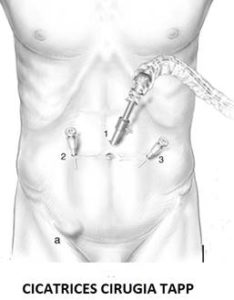

Ya desde hace unos pocos lustros, se ha observado que la cirugía mínimamente invasiva también puede ser usada para el tratamiento quirúrgico de la hernia inguinal. Hay 2 variedades de cirugía mínimamente invasiva de la hernia. La que se entra completamente en la cavidad abdominal (TAPP o laparoscópica) y la que nos deslizamos por detrás de la musculatura del abdomen sin llegar a entrar en la cavidad abdominal porque, la última capa, el peritoneo, queda indemne (TEP o endoscópica). Ambas tienen similares resultados, aunque con distintas peculiaridades en sus ventajas o inconvenientes que hacen más aconsejables una u otra según las circunstancias que rodean al paciente.

Ya desde hace unos pocos lustros, se ha observado que la cirugía mínimamente invasiva también puede ser usada para el tratamiento quirúrgico de la hernia inguinal. Hay 2 variedades de cirugía mínimamente invasiva de la hernia. La que se entra completamente en la cavidad abdominal (TAPP o laparoscópica) y la que nos deslizamos por detrás de la musculatura del abdomen sin llegar a entrar en la cavidad abdominal porque, la última capa, el peritoneo, queda indemne (TEP o endoscópica). Ambas tienen similares resultados, aunque con distintas peculiaridades en sus ventajas o inconvenientes que hacen más aconsejables una u otra según las circunstancias que rodean al paciente.

El resultado de la cirugía de la hernia inguinal, tanto por vía abierta anterior como por cirugía mínimamente invasiva, es similar en cuanto a curación de la hernia. Sin embargo, la ventaja de la cirugía TEP o TAPP se observa durante el postoperatorio inmediato. En contraposición a la cirugía abierta tradicional, que conlleva varias semanas de necesidad de reposo por las notables molestias que impiden una vida activa normal, en la cirugía TEP o TAPP la duración y el nivel del dolor postoperatorio es llamativamente menor. Ello permite en la mayoría de los casos el alta hospitalaria casi inmediata, al de escasas horas de la intervención. Además, seguido de un periodo de convalecencia muy reducido o casi inexistente habida cuenta de las escasas molestias que el paciente va a presentar. Consecuencia de esto es la rapidísima incorporación del paciente a su vida laboral y actividad física habitual que va a ocurrir, casi siempre, al de escasos días de la operación.

El resultado de la cirugía de la hernia inguinal, tanto por vía abierta anterior como por cirugía mínimamente invasiva, es similar en cuanto a curación de la hernia. Sin embargo, la ventaja de la cirugía TEP o TAPP se observa durante el postoperatorio inmediato. En contraposición a la cirugía abierta tradicional, que conlleva varias semanas de necesidad de reposo por las notables molestias que impiden una vida activa normal, en la cirugía TEP o TAPP la duración y el nivel del dolor postoperatorio es llamativamente menor. Ello permite en la mayoría de los casos el alta hospitalaria casi inmediata, al de escasas horas de la intervención. Además, seguido de un periodo de convalecencia muy reducido o casi inexistente habida cuenta de las escasas molestias que el paciente va a presentar. Consecuencia de esto es la rapidísima incorporación del paciente a su vida laboral y actividad física habitual que va a ocurrir, casi siempre, al de escasos días de la operación.

Prácticamente casi todos los casos de hernia inguinal son candidatos a cirugía mínimamente invasiva. Incluso aquellos casos de hernias recidivadas, es decir, que les haya vuelto a salir la hernia a pesar de estar ya previamente operados por vía anterior abierta.

Cuando TEP o cuando TAPP:

Siempre estará por delante la preferencia del cirujano que pueda tener más práctica con una que con otra técnica. Lo ideal es dominar ambas técnicas para ofrecer al paciente la que mejor le convenga.

Los perfectos candidatos a la cirugía endoscópica TEP (Total Extra Peritoneal) son aquellos pacientes delgados, o con niveles de sobrepeso leves o moderados. Hernia de tamaño normal, que no sean muy voluminosas. Pueden ser tanto hernias unilaterales o bilaterales.

Se preferirá la cirugía laparoscópica TAPP (Total Abdominal Pre Peritoneal) para aquellos pacientes con manifiesto sobrepeso, hernias de considerable tamaño o que se prevea adherencias del campo quirúrgico por antecedentes previos de cirugía laparoscópica o robótica de la próstata.

Como ya se ha comentado, la principal ventaja de la cirugía laparoscópica o endoscópica de la hernia es la rápida incorporación del paciente a su actividad laboral o actividad física habitual que con alta frecuencia ocurre entre el 2º -4º días de la operación.